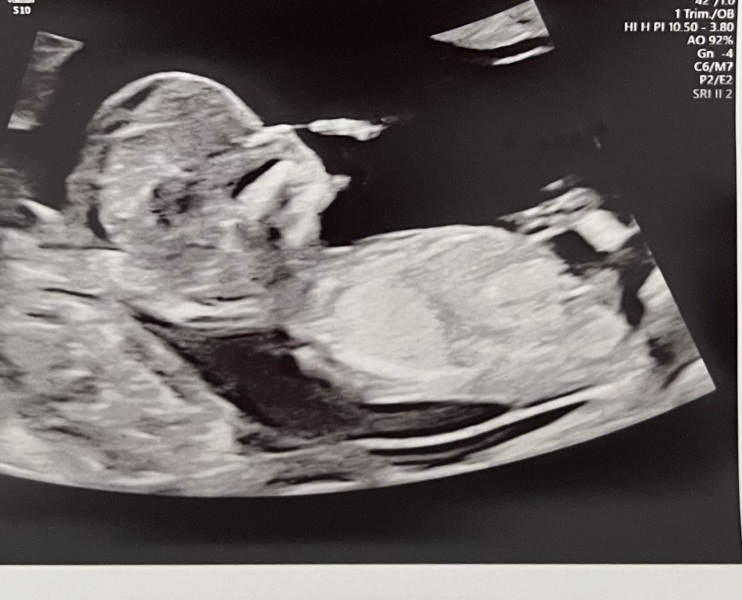

CharlotteB94 · 20/03/2024 17:02

Had 12 week scan today!! So keen for a bit of fun trying to guess the gender :) does anyone have any guesses…?

@CharlotteB94 I think boy

@CharlotteB94 I think boy too 🙊 x

@CharlotteB94 I'd say boy too! I've got mine tomorrow!